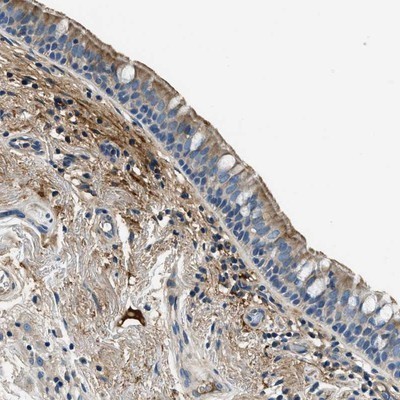

Supportive validation

- Submitted by

- Novus Biologicals (provider)

- Main image

- Experimental details

- Immunohistochemistry-Paraffin: TMEM186 Antibody [NBP1-88452] - Staining of human bronchus shows moderate cytoplasmic and membranous positivity in respiratory epithelial cells.